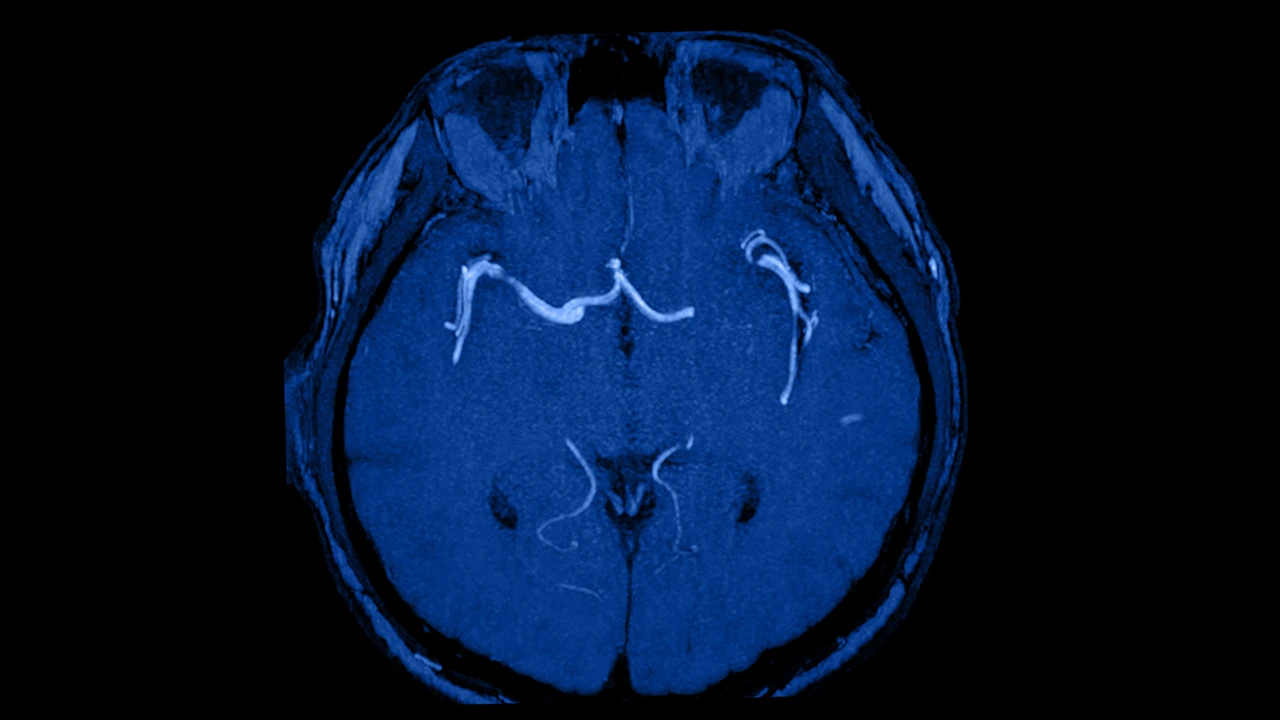

Diagnóstico temprano mediante imagenología

Los chequeos periódicos mediante Doppler carotídeo o resonancias magnéticas pueden detectar estenosis (estrechamiento de arterias) antes de que causen síntomas. El diagnóstico preventivo permite realizar procedimientos como la colocación de stents o endarterectomías que limpian la arteria antes de una obstrucción total.